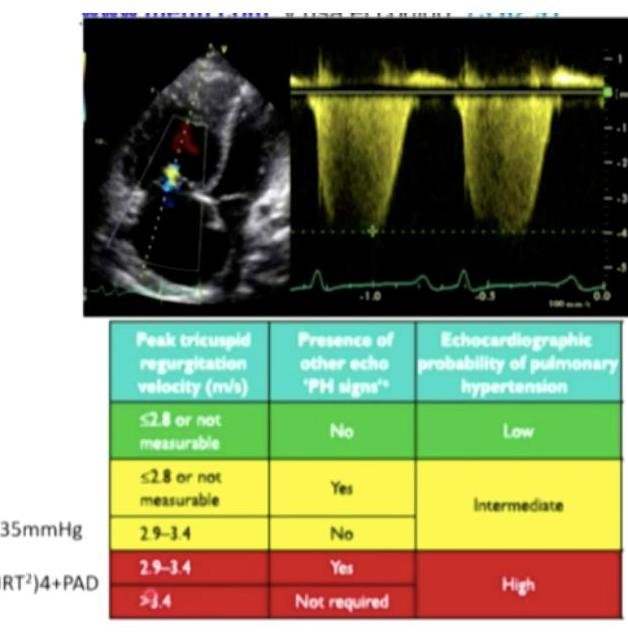

# HIPERTENSIÓN ARTERIAL PULMONAR ## DEFINICIÓN Se define **hemodinámicamente** como una **presión de arteria pulmonar media mayor de 25 mmHg** (3.3 kPa) y una **presión capilar pulmonar menor de 15 mmHg** medidas por **cateterismo cardiaco derecho** con **gasto cardiaco normal o bajo**. En las **arterias pulmonares** hay **fibrosis** en la **capa íntima** y **engrosamiento** en **capa media**, que genera **obstrucción** y **posteriormente trombosis**. **Hipertensión Arterial Primaria:** **Hipertensión Pulmonar** sin **causa conocida**, caracterizada por un **aumento progresivo** de la **presión pulmonar arterial** y de las **resistencias pulmonares**. ## CLASIFICACIÓN | CLASE | ETIOLOGÍA | | :--: | :-- | | 1 | Idiopática, primaria o hereditaria (mutación en el gen BMPR2) | | 2 | Cardiopatía izquierda (disfunción sistólica, diastólica y enfermedad valvular). | | 3 | Enfermedad pulmonar crónica (EPOC) o Hipoxia (SAOS, vivir en altitudes elevadas) | | 4 | Tromboembólica crónica | | 5 | Multifactorial (hematológica, sistémica, metabólica) | ## CLÍNICA - Disnea progresiva al realizar ejercicio - Dolor torácico - Debilidad o fatiga - Síncope con el ejercicio - Hepatomegalia - Edema en extremidades inferiores - Hipotensión (por bajo gasto cardiaco) - Cianosis - Segundo ruido pulmonar reforzado - Soplos cardiacos (insuficiencia tricuspídea) ## CLASES FUNCIONALES DE LA OMS | CLASE FUNCIONAL | SINTOMATOLOGÍA | | :--: | :-- | | I | Síntomas mínimos, sin limitaciones en actividad física | | II | Leve limitación a la actividad física | | III | Marcada limitación a la actividad física | | IV | Incapacidad a la actividad física con o sin síntomas en reposo | # DIAGNÓSTICO ## GOLD STANDARD: CATETERISMO CARDIACO DERECHO (CDD) Se realiza con un **Catéter de Swan-Ganz**. - **Presencia** de **Presión Arterial Pulmonar Media > 25 mmHg** - **Presión Capilar Pulmonar menor a 15 mmHg** - **Gasto cardiaco normal o bajo** ## PRUEBA DE VASORREACTIVIDAD Se debe realizar al momento del **diagnóstico** en **idiopática**, **hereditaria** y asociada a **drogas**. - **Fármacos** utilizados: **óxido nítrico inhalado, Epoprostenol IV, Adenosina IV** - Es **positiva** cuando hay una **disminución** de **mayor o igual a 10 mmHg de la PAPm** o un **valor absoluto de PAPm menor a 40 mmHg** En esta **prueba**, solo el **10 %** responden a la **vasoreactividad** y solo la mitad a **largo plazo**. ## ECOCARDIOGRAMA TRANSTORÁCICO **Estudio de tamizaje** para **Hipertensión pulmonar**, **sensibilidad 87 %**, **especificidad 72 %** - **Presión arterial sistólica** de la **arteria pulmonar > 36 mmHg** - **Regurgitación tricuspídea > 3 lpm** - Cambios en **cavidades derechas** (**hipertrofia del ventrículo derecho**) ## ELECTROCARDIOGRAMA **Datos** de **HVD** y **desviación del eje a la derecha**.  ## CAMINATA DE 6 MINUTOS - **Prueba estandarizada, confiable y reproducible** - Útil para **correlacionar directamente** con la **clase funcional**, la **hemodinámica** y la **sobrevida** de pacientes con **HAP**. # TRATAMIENTO ## 1ra elección: FARMACOLÓGICO ## VASORREACTIVIDAD POSITIVA - **Bloqueadores de los canales de calcio** (**Amlodipino** o **Nifedipino**) ## VASORREACTIVIDAD NEGATIVA - **Inhibidores 5-fosfodiesterasa** (**Sildenafilo**) - **Antagonistas del receptor de la endotelina** (**Bosentán**) - **Análogos de prostaglandinas** (**Epoprostenol** o **Iloprost**). ## MEDIDAS GENERALES: - **Oxígeno suplementario** para mantener **SpO₂ > 90 %** - **Anticoagulación** para evitar **trombos** - Tratar **enfermedad subyacente**. ## 2da elección: QUIRÚRGICO ## SEPTOTOMÍA AURICULAR CON BALÓN - **Clase funcional IV** - **Falla terapéutica** - **Puente para trasplante** ## TRASPLANTE PULMONAR - **Pobre pronóstico** - **Falla cardiaca refractaria a tratamiento** - **Clase funcional III y IV** ## PRONÓSTICO Con **vasorreactividad positiva**: **Supervivencia del 95 % a 5 años**. **Mal pronóstico** si hay **daño** en **ventrículo derecho**. ## REFERENCIA Referir a **tercer nivel** para **manejo** y **seguimiento**